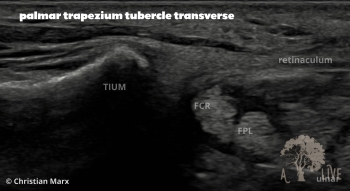

carpal ligaments